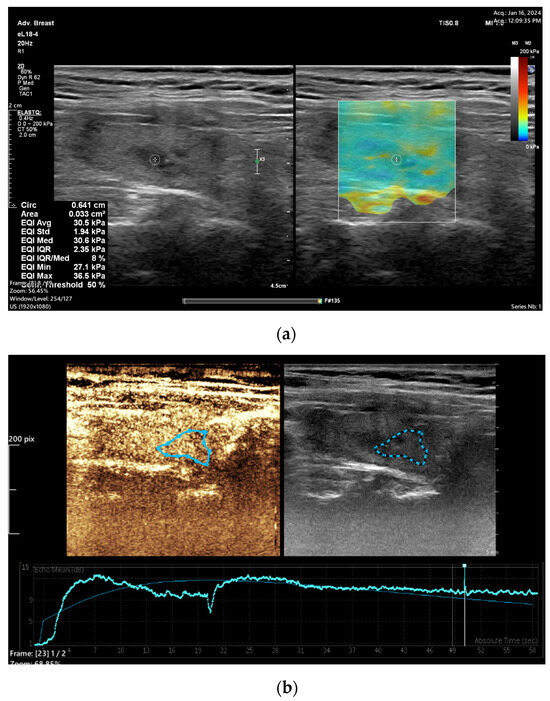

In recent years, many research papers have demonstrated that multiparametric evaluation of focal thyroid lesions using conventional US in association with elastography and CEUS enhances the sensitivity and specificity of ultrasound in predicting thyroid malignancy (Figure 1 and Figure 2).

Figure 1.

A 66 year old female with papillary thyroid carcinoma overlapped with Hashimoto thyroiditis. (a) Quantitative shear wave elastography (SWE) revealed 30.5 kPa; (b) qualitative contrast-enhanced ultrasound (CEUS) of the nodule revealed homogenous hyper-enhancement and quantitative CEUS revealed a time to peak of 20.3 s and a peak intensity of 11.58 dB.